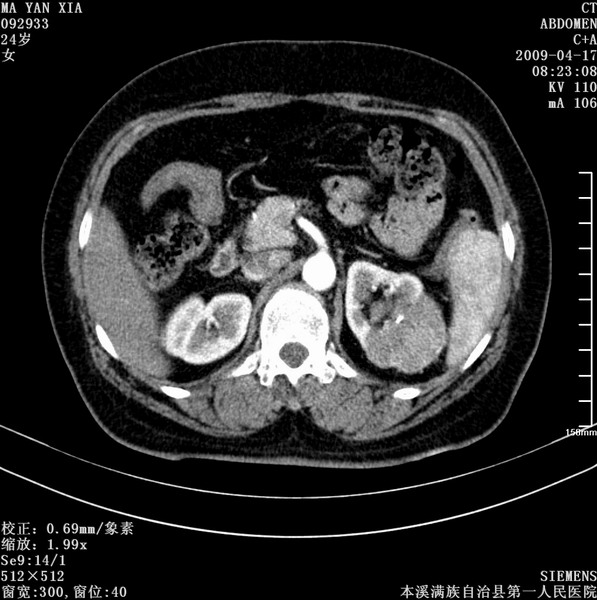

标题: CT19443:肾脏肿瘤两个区强化不一样。 [打印本页]

标题: CT19443:肾脏肿瘤两个区强化不一样。

女,51岁,体检时发现肾脏占位,建议ct增强。无任何自觉症状。

首先考虑左肾癌.

肾盂癌或肾癌侵犯肾盂

左侧肾癌侵犯肾盂。

典型的不均匀强化,左肾癌